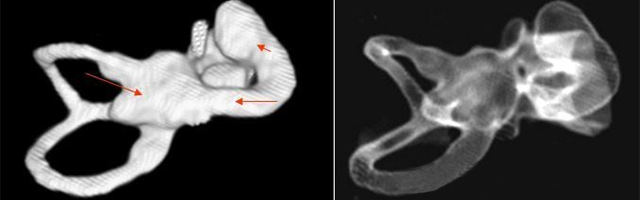

1、診斷

主要依靠顳骨高分辨CT和內耳MRI。

雙側內耳畸形:左側無內耳迷路及內耳道機構,為米歇爾畸形;右側空耳蝸及前庭擴大,為先天性耳蝸畸形